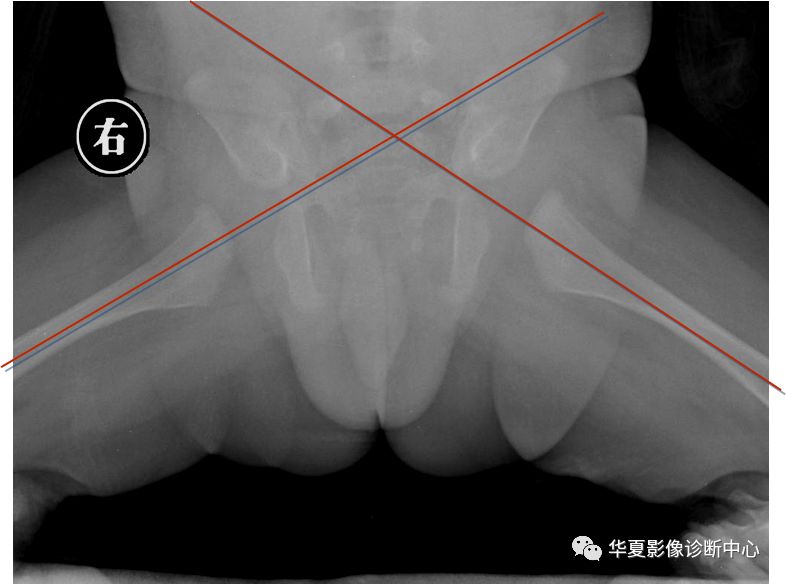

1.Von-Rosen (外展内旋位)摄片法

婴儿仰卧位,双下肢外展45度,尽力内旋位摄片。

正常时骨干轴线向上的延长线经髋臼外缘相交于腰5与骶1的平面以下。但脱位时此线经髂前上棘相交于腰5骶1平面以上。